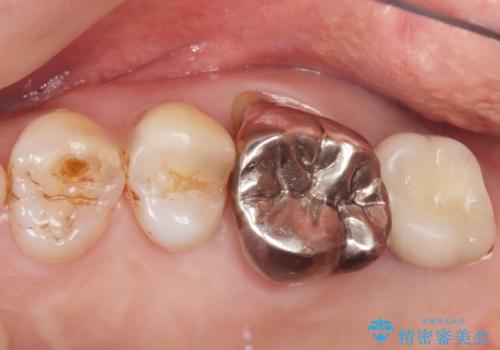

- 奥歯が咬むと痛い、熱いものがしみることを主訴に来院された患者様です。

奥歯(左上7)のメタルインレー(銀の詰め物)を除去し精査したところ、奥歯はわれていました。

根尖近くまで深くヒビが入っており保存不可能な状態でした。